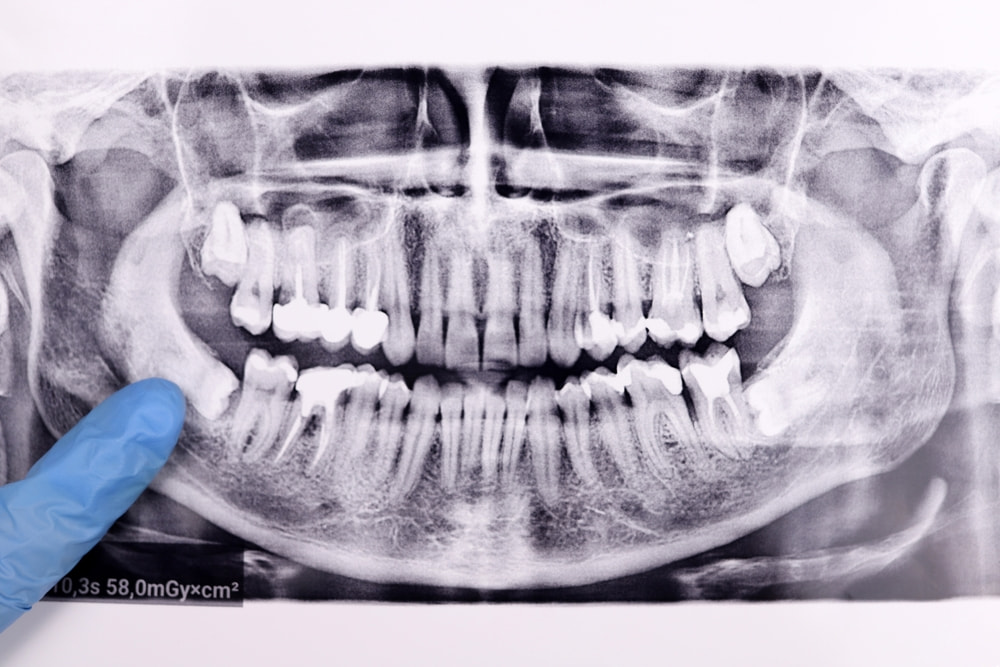

Wisdom teeth can sit close to nerves in the jaw, which is why some patients are concerned about nerve damage.

The good news is that this is uncommon when the procedure is performed by an experienced provider. Careful imaging and planning are used to protect nearby nerves during extraction.